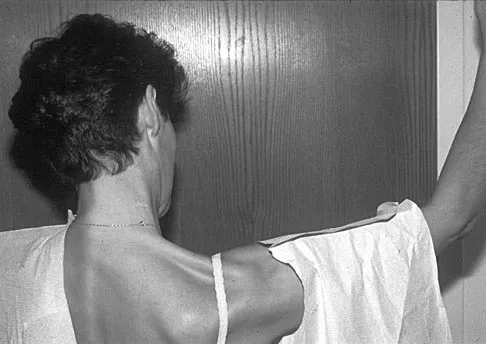

A 36-year-old woman has pain and swelling of the anterior arm after undergoing arthroscopic shoulder surgery 8 months ago. At the time of the procedure, extensive debridement and synovectomy of the anterior aspect of the joint was performed to remove scar tissue that had formed after an open rotator cuff repair. Examination reveals a golf ball-sized swelling just lateral to the coracoid. The area is not warm and shows no other signs of infection. An MRI scan is shown in Figure 1. Management should now consist of

Figure 17 shows the clinical photograph of a 45-year-old female tennis player who has right arm pain and weakness with elevation after undergoing a cervical biopsy several months ago. The cause of her shoulder weakness is damage to the